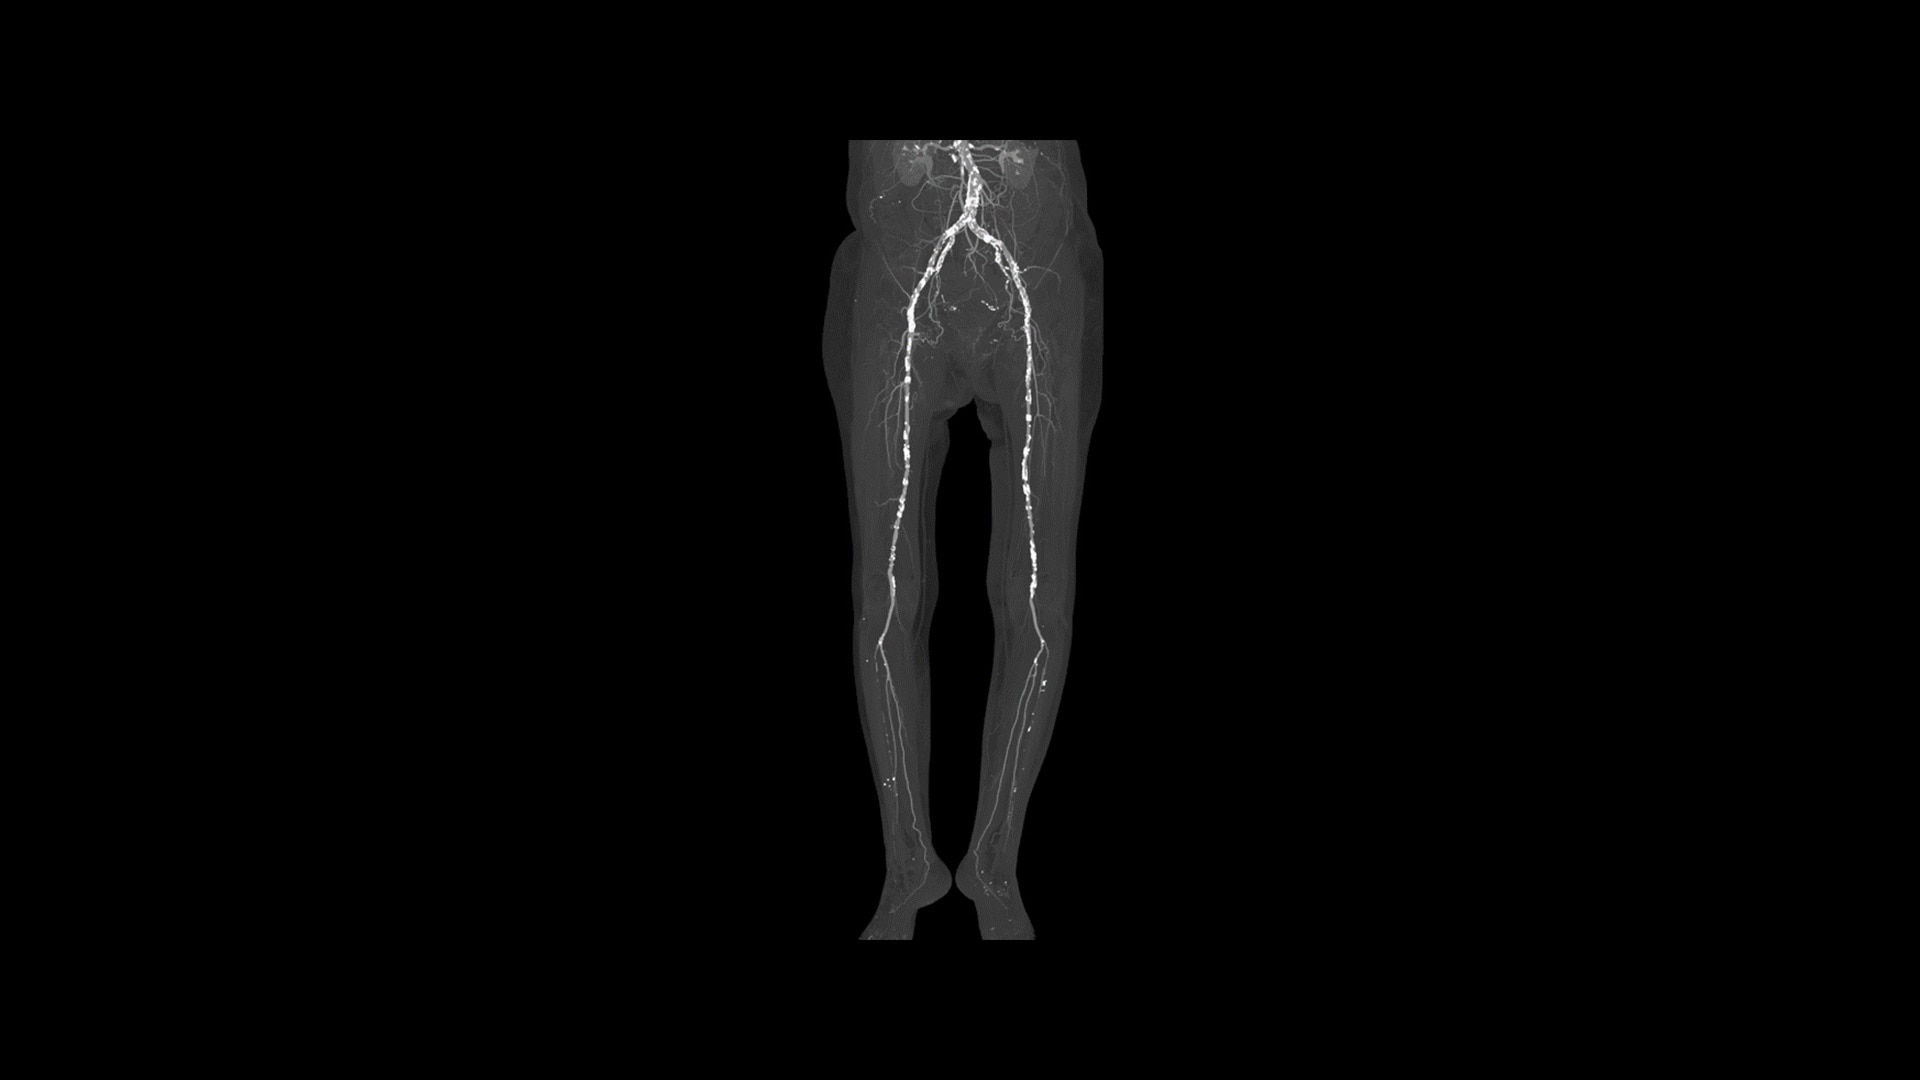

You’ll be ready for what’s next

The Revolution Ascend Platform’s scalable and upgradeable design lets you invest in the clinical capabilities you need today, while enabling your CT to grow with you in the future. The Revolution Ascend Select can be upgraded to Plus or Elite. And Plus can be upgraded to Elite. All of the configurations are paired with Effortless Workflow and Smart Subscription for the most efficient CT experience.

Revolution Ascend Select

High performance for routing and basic coronary analysis

20 mm coverage

32/64 slices

Upgradable to Plus

Revolution Ascend Plus

Best-in-class with a faster workflow from referral to report

40 mm coverage

64/128 slices

Upgradable to Elite

Revolution Ascend Elite

State-of-the-art detectability and diagnosis

128 slices

Comes standard with deep learning technologies